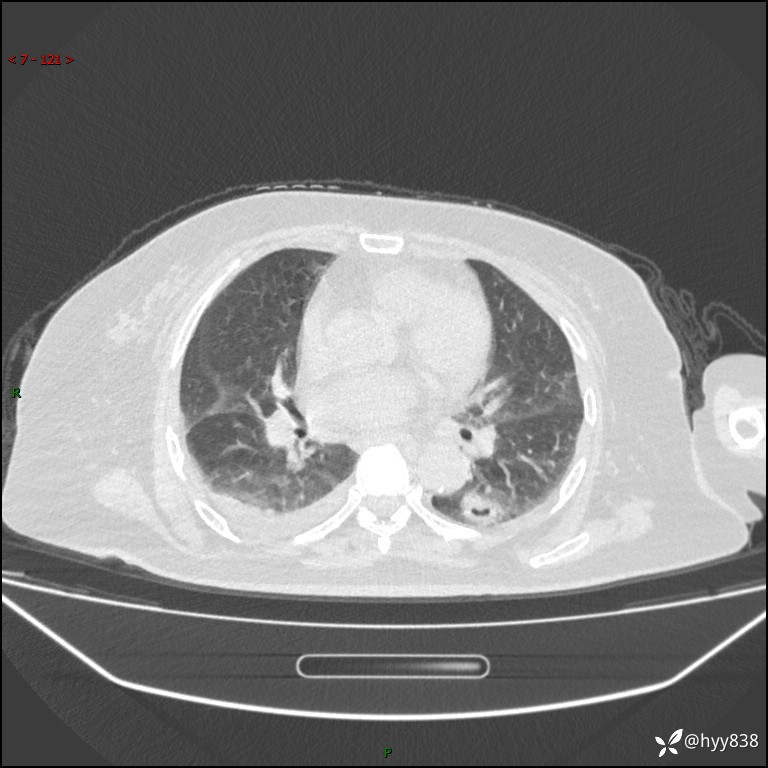

患者性别:女

患者年龄:57岁

简要病史:昏迷入院

临床诊断:昏迷

胸部 CT平扫、